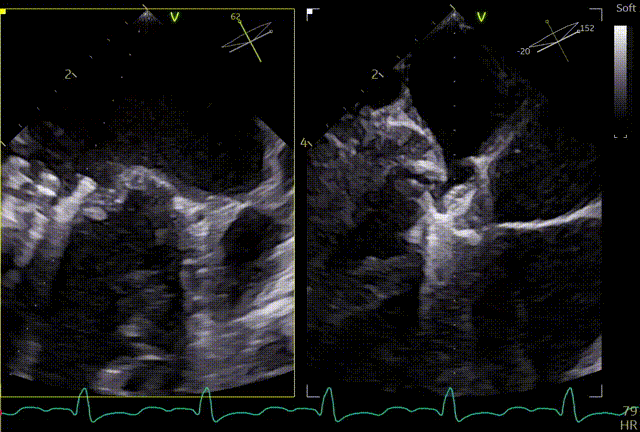

术前心超团队王蓓教授以及余婵教授对患者的瓣膜解剖情况进行了详细的评估:

① 二尖瓣后叶广泛栓系,前后叶对合不良,二尖瓣重度关闭不全,Carpentier分型Ⅲb,反流程度4+;

② 画迹法显示二尖瓣瓣口面积5.25cm²,平均跨瓣压差4.2mmHg;

③ 二尖瓣前叶(A1)长度28.5mm,二尖瓣后叶(P1)长度: 10.4mm;二尖瓣前叶(A2)长度28.4mm,二尖瓣后叶(P2)长度: 12.7mm二尖瓣前叶(A3)长度22.6mm,二尖瓣后叶(P3)长度: 11.5mm;

④ 3区前后叶对合gap 4.5mm,2区前后叶对合gap 3mm。

术前TTE

两腔心

短轴

四腔心zoom模式

反流情况